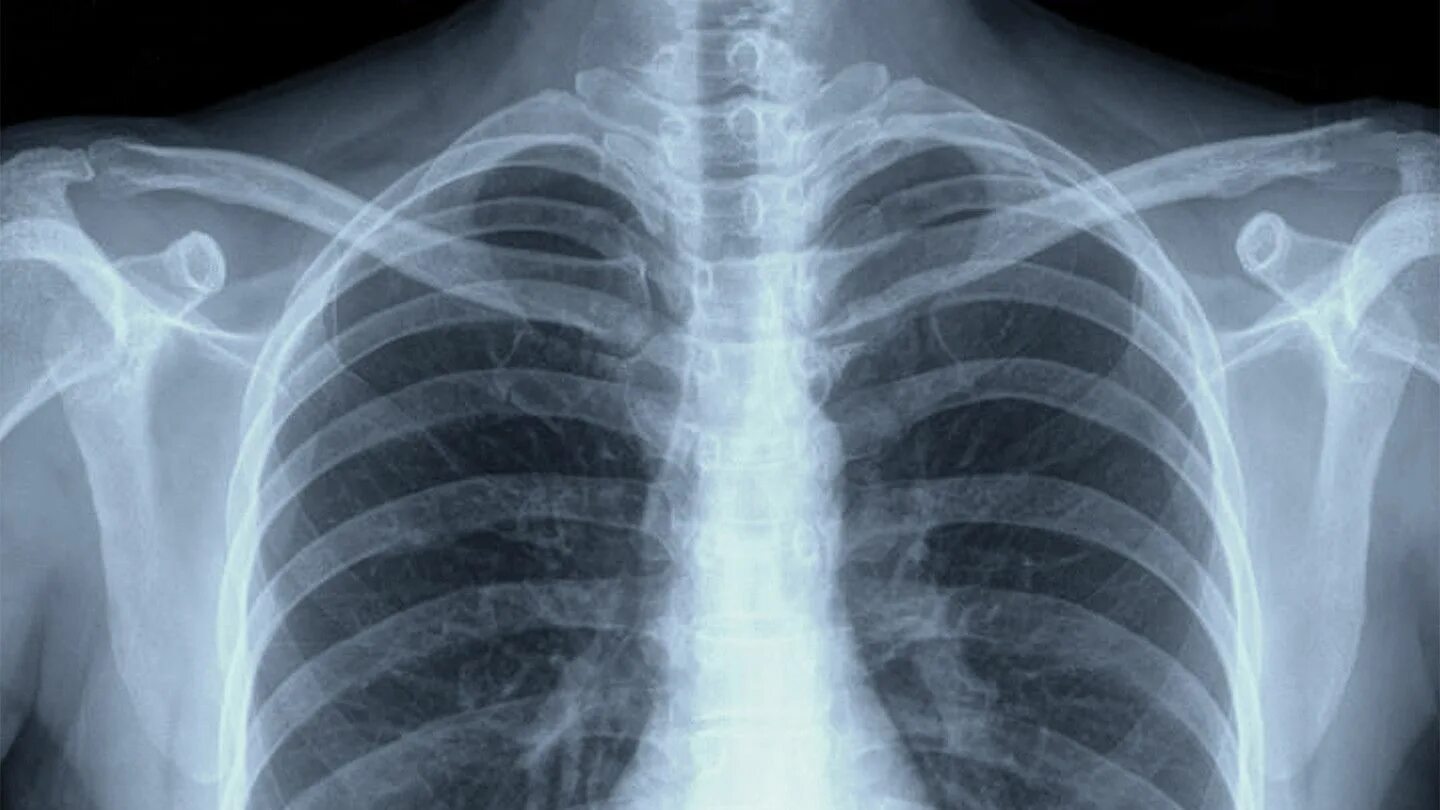

Почему в легких